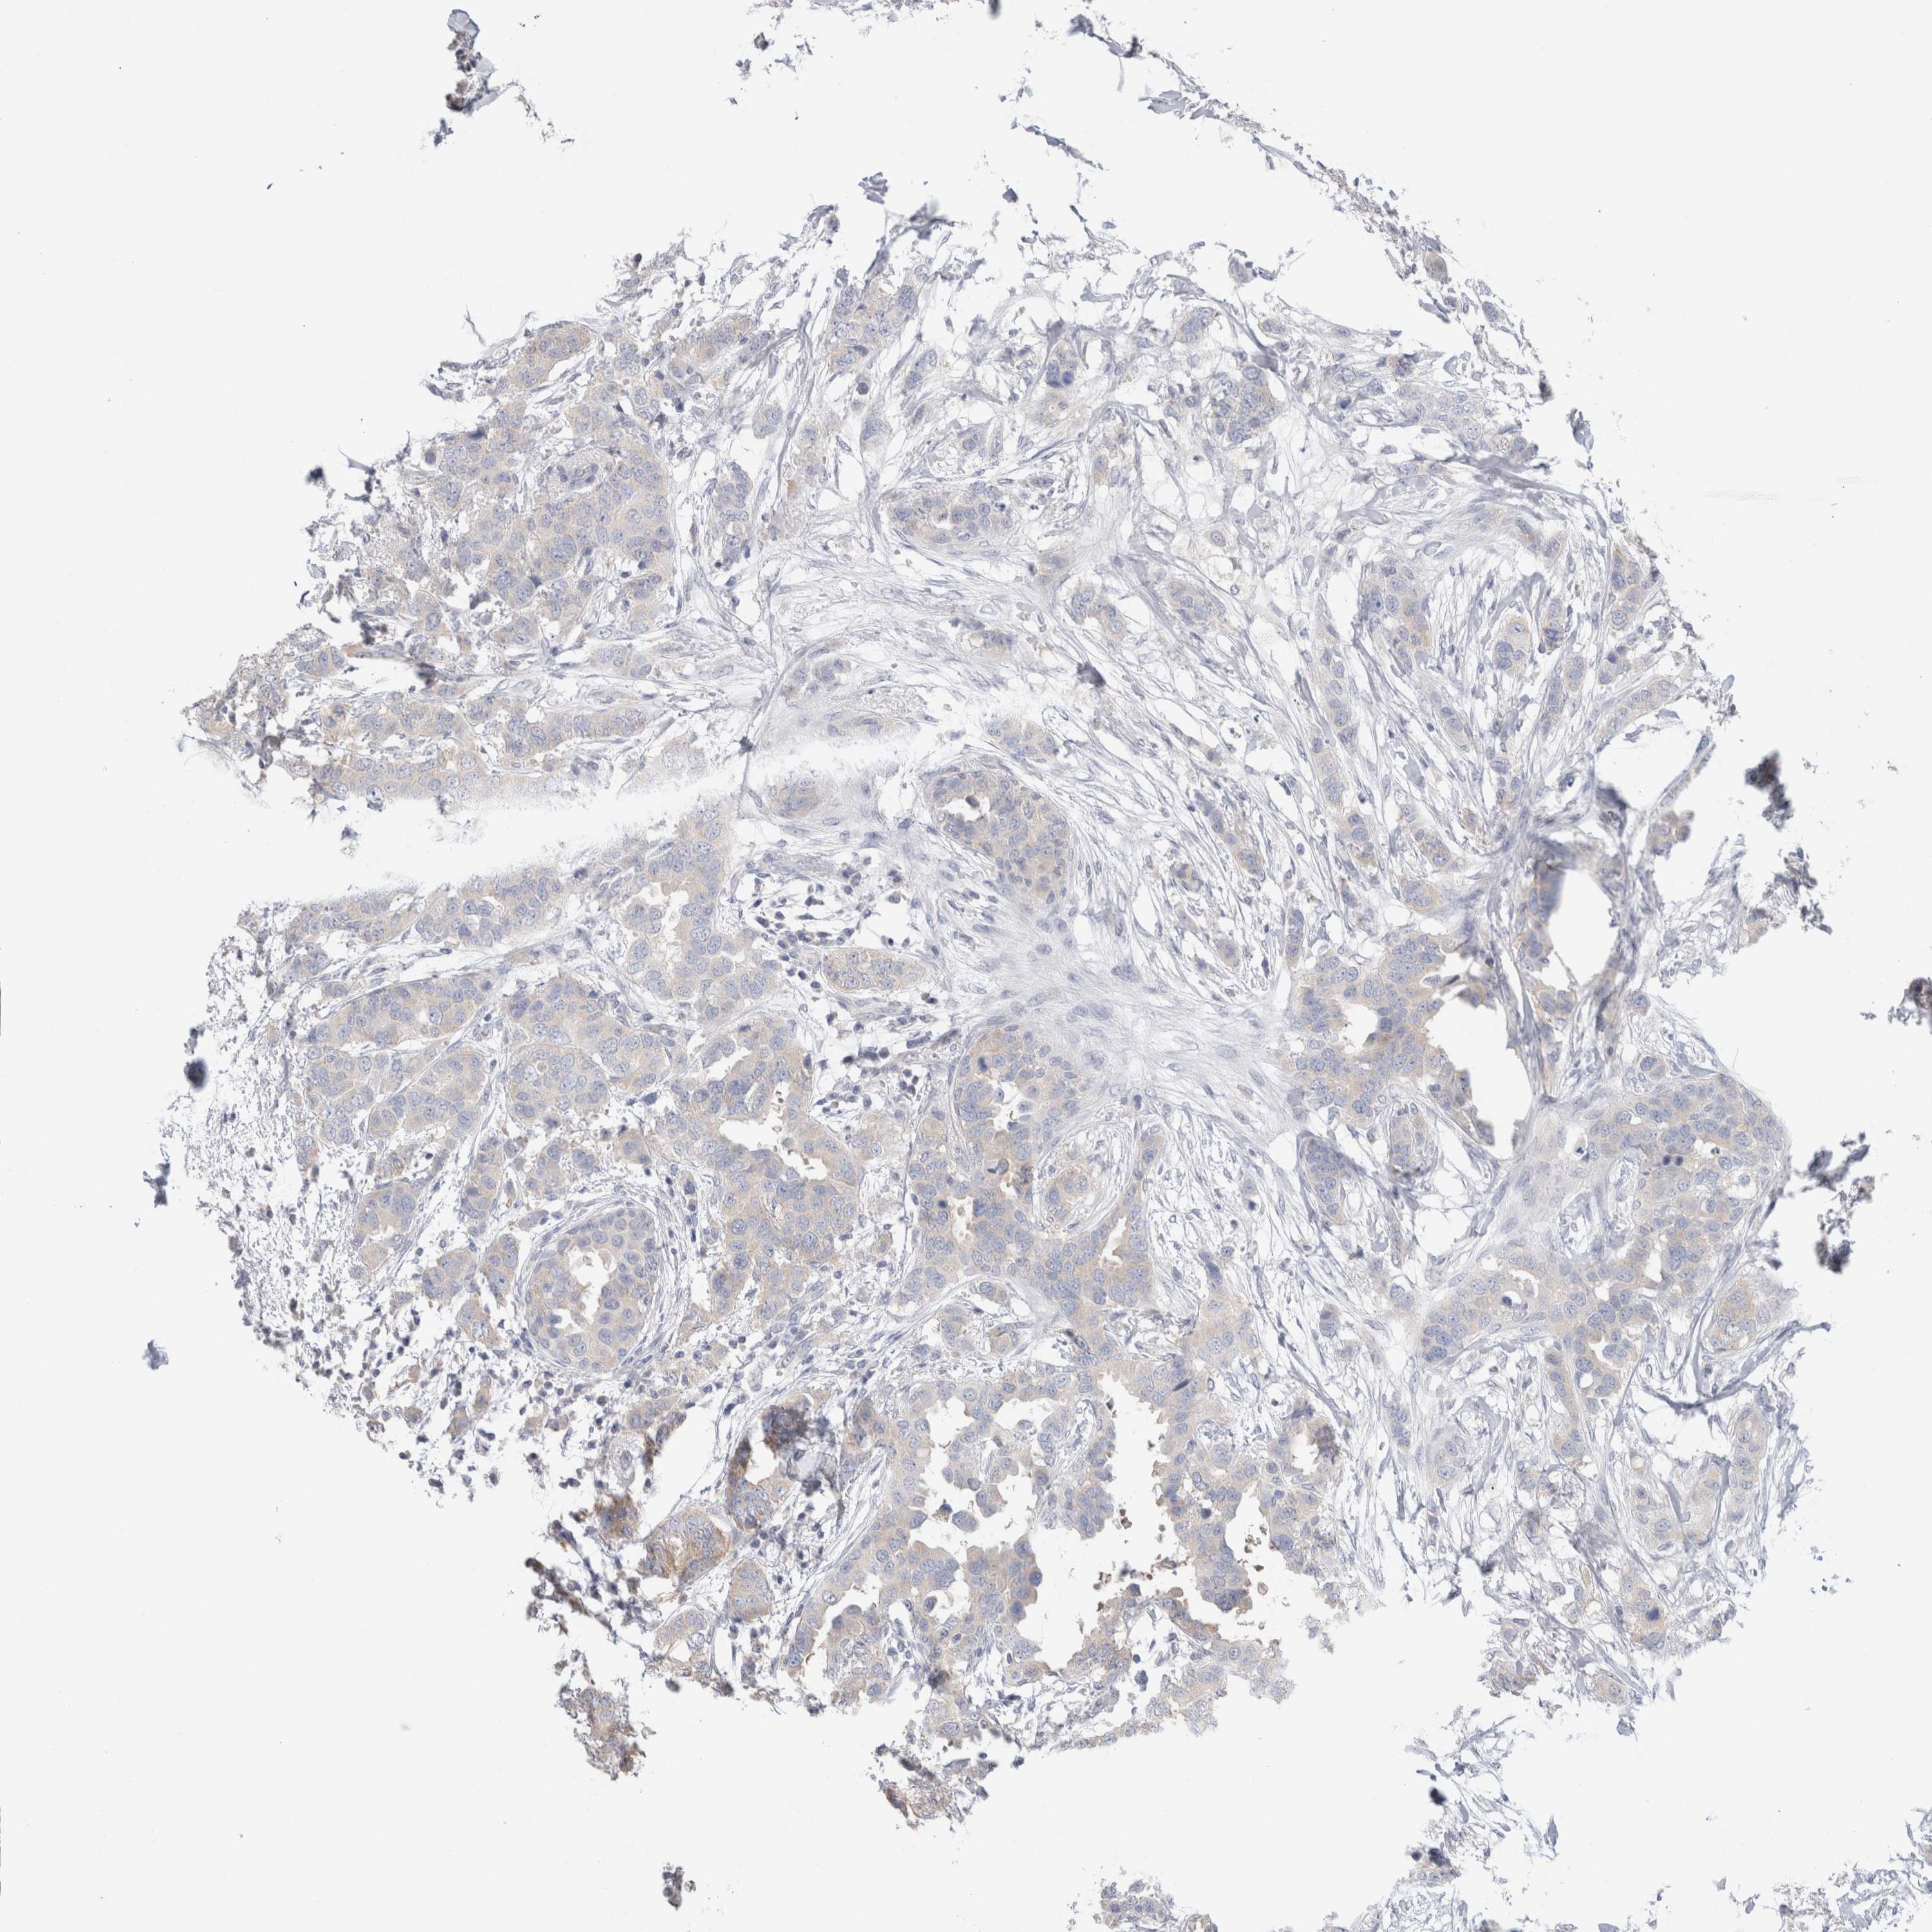

CANCER BREAST CANCER Show tissue menu

BRCA TCGA BRCA VALIDATION PROTEIN EXPRESSION